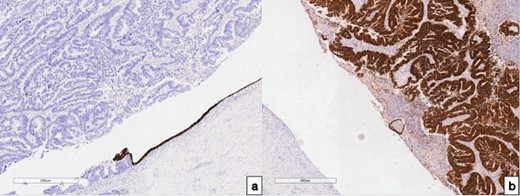

In order to determine the tumor origin, immunohistochemical (IHC) analyses (Fig. 3) and hematoxylin and eosin staining (HE) were conducted. The HE revealed adenocarcinoma growth in the fallopian tube wall. Subsequent IHC examination on demonstrated diffuse expression of Caudal type homeobox 2 (CDX 2) and Keratin 20 (CK 20) in tumor cells within the fallopian tube and uterine corpus. Conversely, Keratin 7 (CK 7) exhibited negative staining in tumor cells within the fallopian tube. However, CK 7 displayed positive staining in preserved endo-salpinx and endometrium cells. Both HE and IHC (CK 20+/CK 7-, CDX 2+ in tumor cells) observations collectively support the conclusion that the tumor metastasized to the fallopian tube from colorectal cancer.

Immunohistochemical examination of the fallopian tube tumor; (a) with antibodies to CK 7, 100× magnification; (b) with antibodies to CDX 2, 100× magnification, and IHC analysis revealed positive CK 7 expressions in the preserved endometrium, while expression was notably absent in the tumor cells; conversely, positive CDX 2 expression was observed in the tumor cells, with an absence of expression noted in the endo-salpinx.